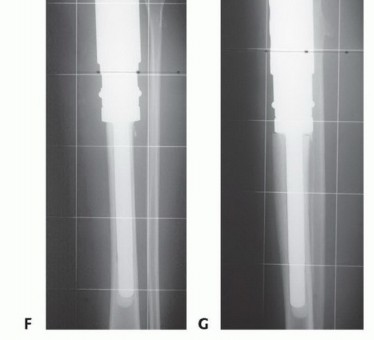

- الاستبدال بالطرف الصناعي (Prosthetic Replacement): هذا هو الخيار المفضل في عيادة الأستاذ الدكتور محمد هطيف. توفر الأطراف الصناعية نتائج وظيفية أفضل بكثير وتقلل من مخاطر عدم الالتئام والعدوى مقارنة بالطعوم العظمية.

دور سديلة العضلة التوأمية الإنسية (Gastrocnemius Rotational Flap)

يُعد استخدام سديلة العضلة التوأمية الإنسية (عضلة الساق) عاملاً رئيسياً في تحقيق تغطية كافية للأنسجة الرخوة للطرف الصناعي واستعادة وظيفة آلية المد. تُنقل هذه العضلة لتدور إلى الأمام لتغطية الطرف الصناعي، مما يقلل بشكل كبير من خطر العدوى ومضاعفات الجروح، وهو ما كان يمثل تحدياً كبيراً في الماضي. يؤكد الأستاذ الدكتور محمد هطيف على أن هذه التقنية أصبحت إجراءً روتينياً وموثوقاً لضمان تغطية الطرف الصناعي وتقليل معدل العدوى ونخر السديلة والبتر الثانوي.

- استئصال الورم: إزالة الجزء المصاب من قصبة الساق والأنسجة المحيطة به مع هامش أمان كافٍ.

- إعادة بناء العيب الهيكلي ومفصل الركبة: زرع طرف صناعي أو طعم عظمي لاستبدال الجزء المستأصل.

- إعادة بناء آلية المد وتغطية الطرف الصناعي بالأنسجة الرخوة: استخدام سديلة العضلة التوأمية لضمان التغطية والحفاظ على وظيفة الركبة.